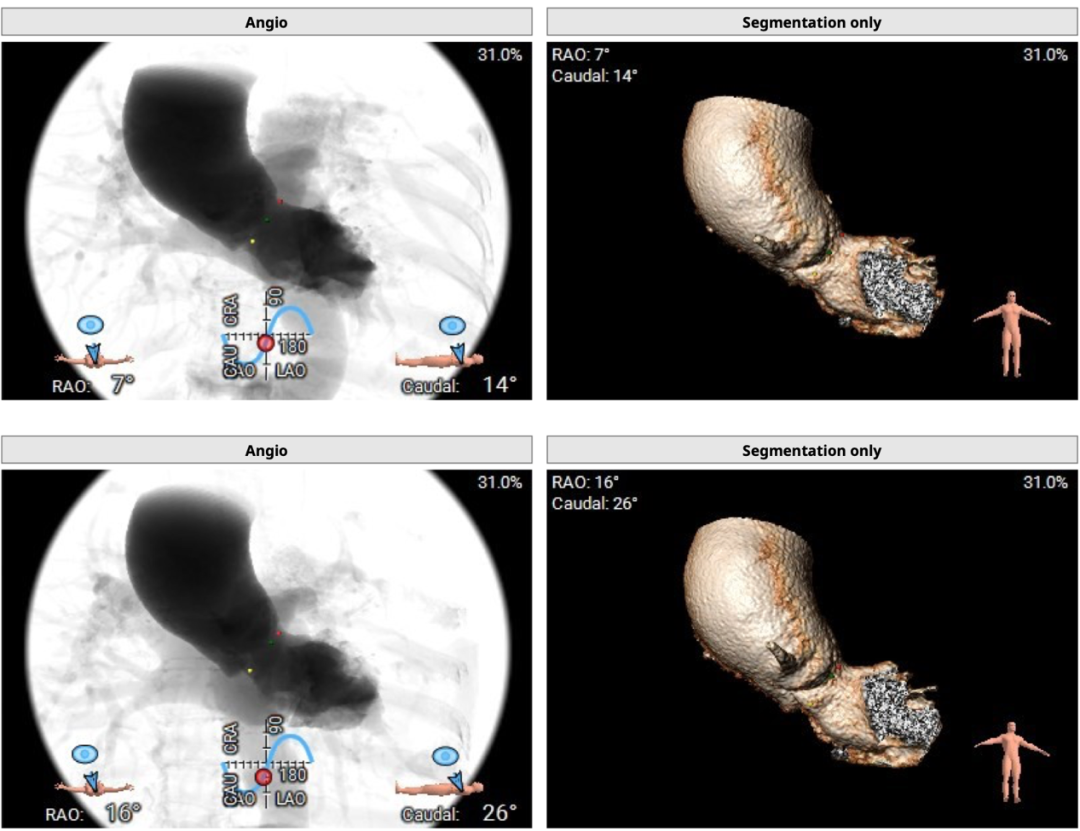

术中建议造影角度RAO 7°,CAU 14°(其它参考角度如下图):